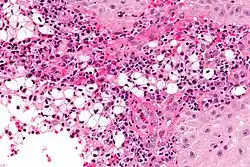

Photogravure of rhinoscleroma from Wolkowitsch. | |

A positive culture in MacConkey agar is diagnostic, but cultures are only positive in 50–60% of cases. Diagnostic characteristics are most commonly found in the granulomatous stage and are described as being plasma cells with birefringent inclusions, Russell bodies, pseudoepitheliomatous hyperplasia, and groups of large vacuolated histiocytes containing Klebsiella rhinoscleromatis (Mikulicz cells).[2]